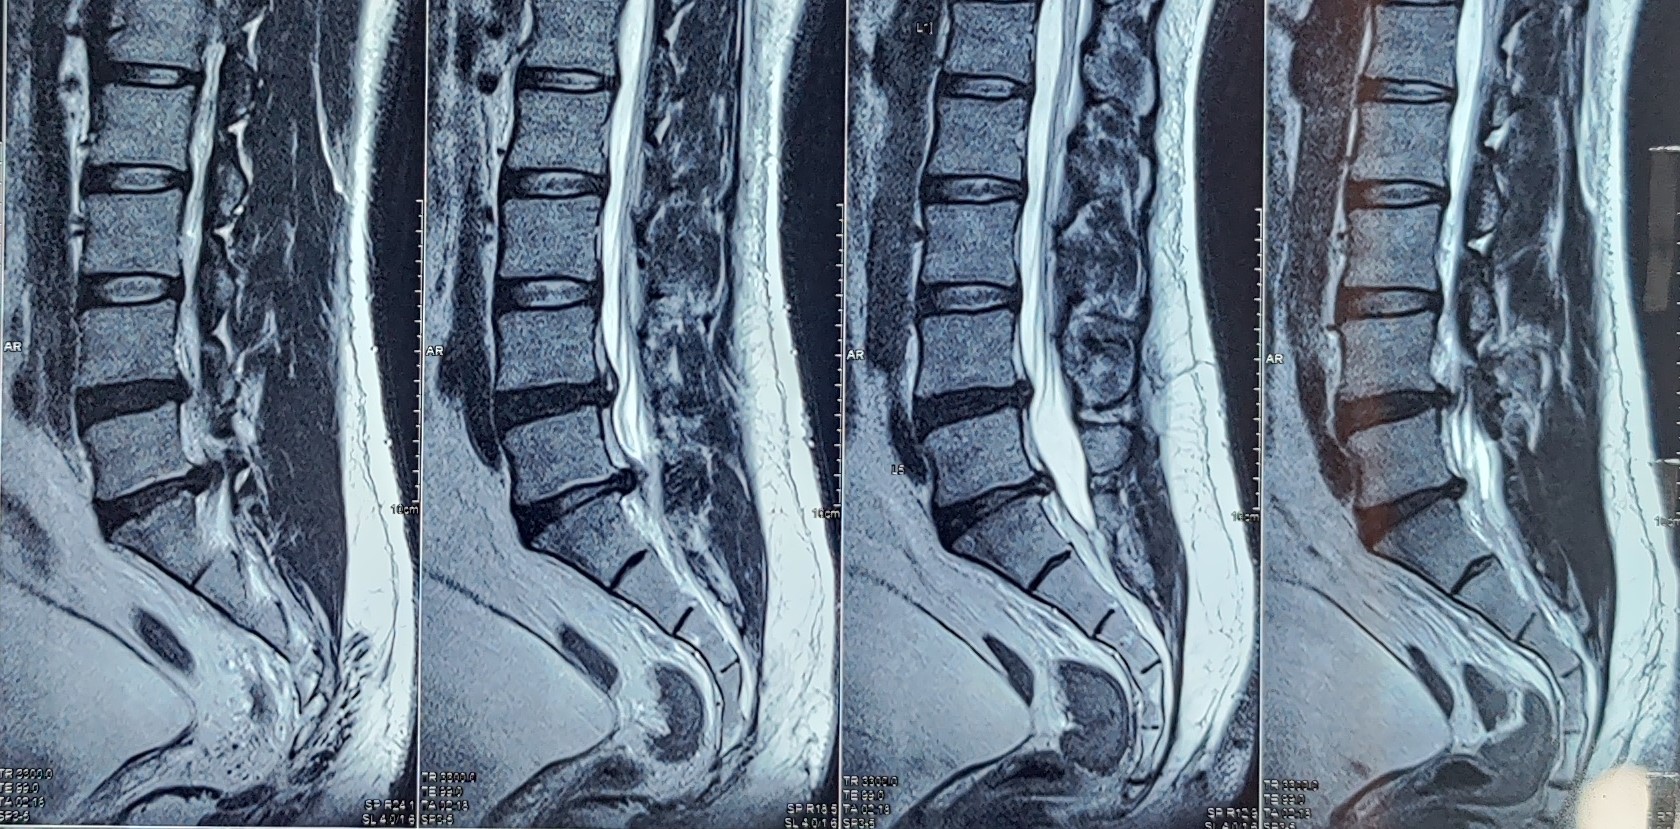

• Prolapsed Intervertebral disc disease

• Chronic back pain with multiple level disc disease

• Spinal stenosis with radicular pain

• Compression fracture of vertebra with radicular pain

Pain associated with the above mentioned conditions is mainly due to the nerve irritation caused by the prolapsed disc or in case of Post-herpetic neuralgia the inflamed Dorsal root ganglia. Instillation of medications close to the irritated nerve reduces the swelling around the nerve, bringing about reduction in the pain.

Most patients need only one injection, however, some patients with big disc may need repetition of the procedure. Decision to repeat the procedure is taken by your doctor looking at your MRI and the relief percentage from previous procedure.